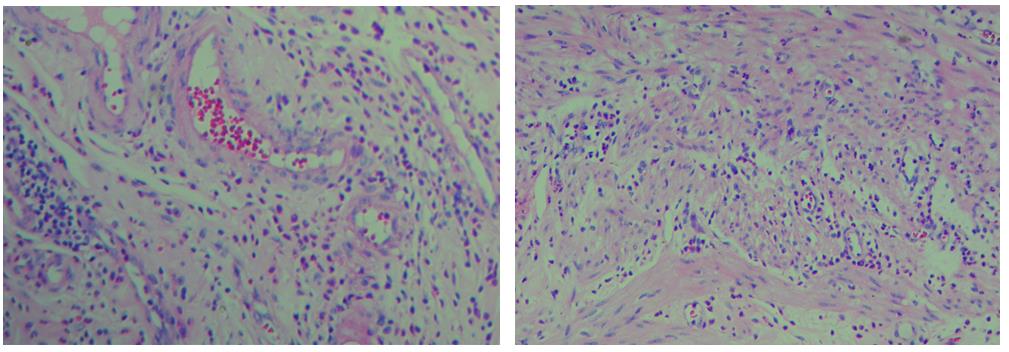

3、色彩鮮艷,核漿紅藍(lán)對(duì)比鮮明,染色效果持久穩(wěn)定,胞核結(jié)構(gòu)清晰

適用于各種細(xì)胞、組織石蠟切片、冰凍切片、火膠棉切片、樹(shù)脂切片、涂片、印片的染色,用于臨床病理學(xué)輔助診斷

細(xì)胞中的細(xì)胞核由帶負(fù)電荷的酸性物質(zhì)組成,與帶正電荷的堿性染料蘇木素的氧化物三氧化蘇木紅有較強(qiáng)的親和力;而細(xì)胞漿則相反,因含有帶正電荷的堿性物質(zhì)而與帶負(fù)電的酸性染料曙紅Y的親和力較強(qiáng);細(xì)胞或組織切片經(jīng)HE染色后,細(xì)胞核被染成藍(lán)紫色,細(xì)胞漿、紅細(xì)胞、肌纖維、膠原纖維、結(jié)締組織、嗜伊紅顆粒等被染成不同程度的紅色、粉紅色或橙紅色,與藍(lán)色的細(xì)胞核形成鮮明的對(duì)比,因此更易于觀察細(xì)胞或組織中正常成份和病變成份的一般形態(tài)結(jié)構(gòu)。

【實(shí)際染色效果】